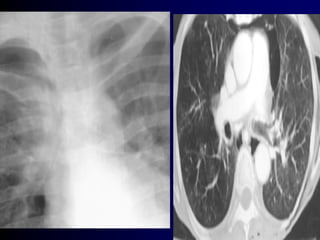

1-Year Therapy With MFNS Did Not Induce

Nasal Atrophy in Patients With PAR1,a

Nasal Biopsies

Before MFNS Treatment After 12 Months of Treatment With

MFNS 200 µg/d

Disruption of epithelium

Eosinophil infiltration

Epithelium intact

No eosinophil infiltration

aThe clinicalrelevance ofthese data in the treatmentofallergic rhinitis is notknown.

MFNS = mometasone furoate nasalspray;PAR= perennialallergic rhinitis.

1. Minshall E et al. Otolaryngol Head Neck Surg. 1998;118:648–654.